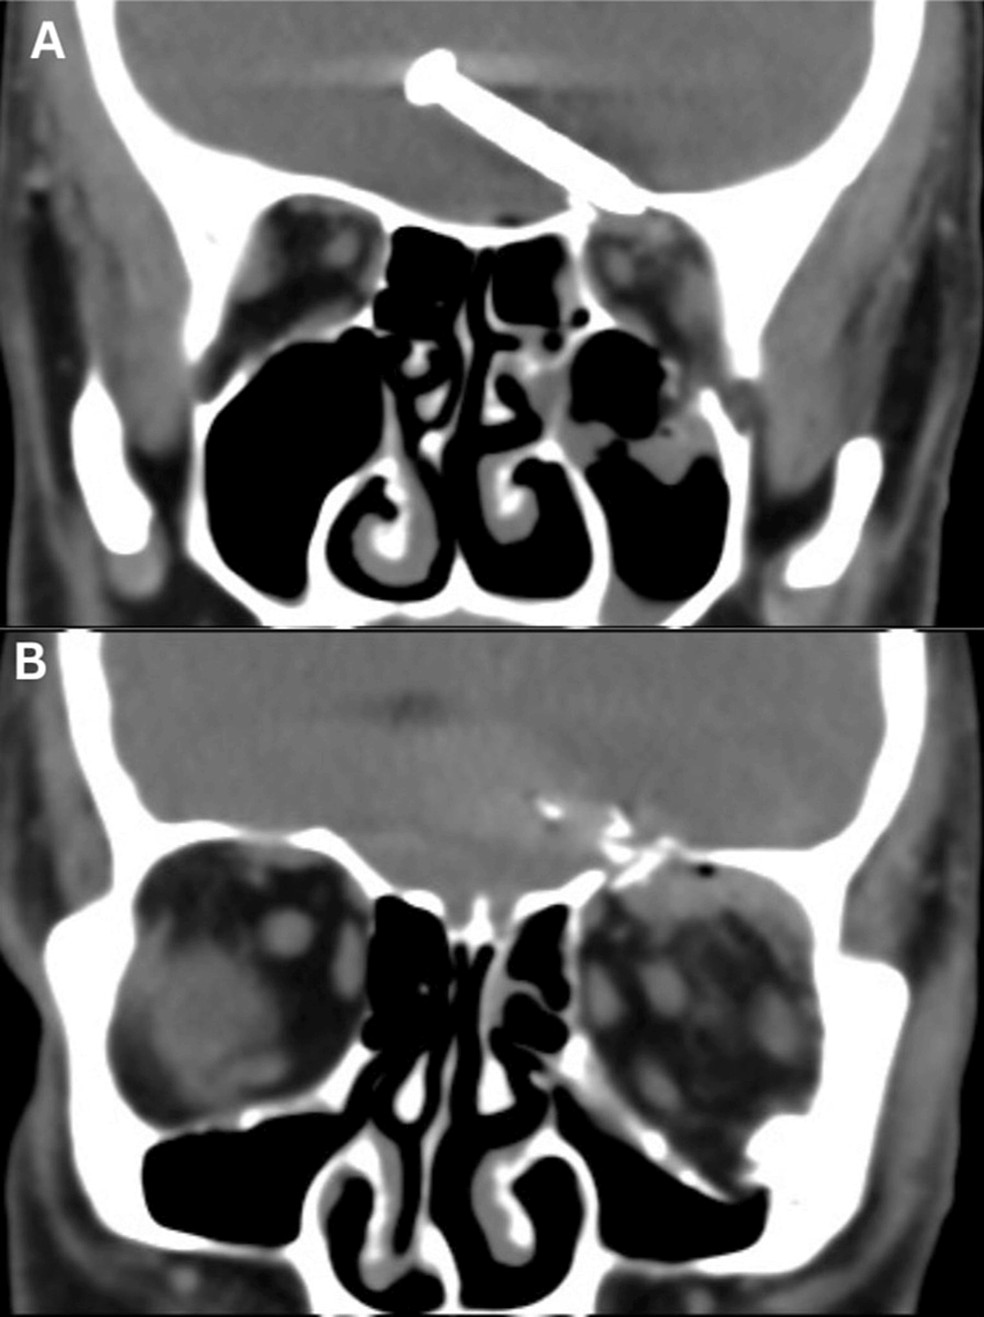

No entanto, logo ficou claro que os danos atingiram muito mais do que o olho. Um raio-X do crânio do homem mostrou que o prego de 3,2 centímetros havia penetrado no lobo frontal do cérebro, fraturando sua órbita ocular conforme entrou na cabeça, com sinais de sangramento se estendendo para regiões cerebrais vizinhas.

O paciente passou por uma cirurgia de emergência para remover o prego. Durante o procedimento, os cirurgiões notaram que “a artéria carótida interna esquerda, as artérias cerebrais anteriores e os nervos olfativos não foram lesionados”, segundo eles relataram.